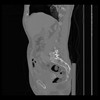

36 CUERPO,CE,Sagittal,3.000,CUERPO,Sagittal,